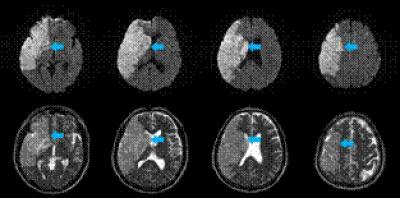

Diffusion-weighted (upper panel) and T2-weighted (lower panel) magnetic resonance images of a 55-year-old male patient with a complete middle cerebral artery territory infarct (arrows).

(Photo Credit: Neural Regeneration Research)